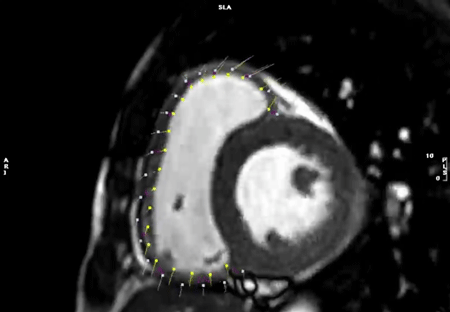

心室全体をカバーする単軸像すべてに対して,心外膜と心内膜の輪郭をトレースすることで,内腔容積を算出する.短軸像を積み重ねることで心室全体の容積が算出できる.拡張末期と収縮末期の両時相において内腔容積を計測することで,拍出量や駆出率などが算出される(Fig. 8).

Pediatric Cardiology and Cardiac Surgery 40(4): 260-271 (2024)

Fig. 8 Left ventricular (LV) and right ventricular (RV) chamber quantification. For LV chamber quantification, the endocardial (red) and epicardial (green) contours are delineated in diastole (left) and systole (right) in a stack of short axis slices that cover the whole left ventricle. For RV chamber quantification, the endocardial (light blue) and epicardial (yellow) contours are delineated. Papillary muscles and cordal tissues are excluded from the LV and RV volume.

左室拡張末期の画像の選択には,全時相の画像を評価して,左室内腔血液容積が最も大きい時相を肉眼的に選択する.選択したある一つの時相の短軸像シリーズ全体(心基部から心尖部にかけて)を拡張末期として適応する.僧帽弁が閉鎖する時相や,大動脈弁の開口直前の時相が左室拡張末期を同定するための参考にもなる.

同様に,左室収縮末期の画像シリーズを左室内腔血液容積が一番少なくなる時相で選択する.また,右室と左室で拡張末期や収縮末期がずれていることがしばしば認められる.その際は左室・右室独立して,それぞれ別の時相での計測をすればよい(機能的・解剖学単心室の場合の取り扱いは後に述べる).

なお,心臓内のスライス位置によって収縮末期がずれることもある.例えば,心基部と心尖部では収縮末期が1時相ずれていることがあり,その際は両時相で左室内腔血液容積を計測し,より小さい容積となる時相を収縮末期と決定する.拡張末期においても同様である.左室同期不全(LV dyssynchrony)においても同様の方法で収縮・拡張末期を決定する.

なお,心内膜だけをトレースすれば心筋重量以外の測定項目(EFなど)をすべて計測でき,解析結果を急ぐ場合には心内膜だけのトレースでもすむが,疾患によっては心筋重量は重要な要素となる.また,本稿後半で触れるようにstrain計測を行うにはきれいな心外膜のトレースが必須である.なお,心外膜のトレースは,画像のコントラストを調整することで周囲組織との境界が明瞭になりトレースが容易となる.

左右心室の拡張末期・収縮末期のタイミングが一致している場合は,左室の計測を行った後に同じ時相(画像)で右室の心内膜・心外膜トレースを行うことができ,心室中隔部分のトレースを省けるため簡便である(心室中隔は左室に含まれる)(Fig. 8).